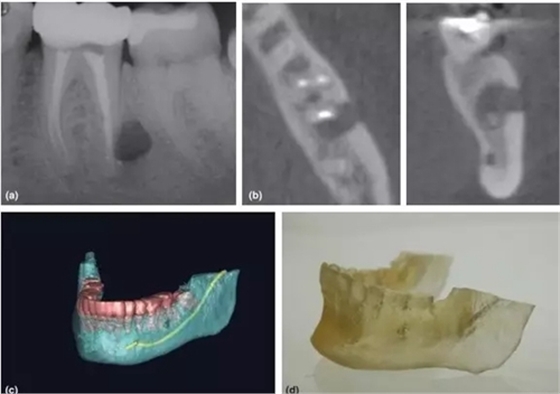

3,根尖周手術(shù)的術(shù)前評(píng)估

CBCT一直被倡導(dǎo)用于評(píng)估和設(shè)計(jì)根尖周手術(shù)方案 (Rigolone et al. 2003; Tsurumachi & Honda 2007; Kim & Kratchman 2006)。三維重建圖像讓臨床醫(yī)生能判斷根尖與鄰近重要解剖結(jié)構(gòu)的關(guān)系,如下頜神經(jīng)管、髁孔和上頜竇等。除外,還能精準(zhǔn)測(cè)量骨損實(shí)際大小、與牙根的關(guān)系、皮質(zhì)骨板厚度、骨開(kāi)窗情況和牙根的傾斜角度(Nakata et al. 2006)。

CBCT掃描還能配合3D打印技術(shù),把掃描的術(shù)區(qū)立體重建并打印出來(lái),得出真實(shí)比例的研究模型,有助于術(shù)者對(duì)手術(shù)方案的設(shè)計(jì)和過(guò)程的演練(Scarfe et la. 2006)。